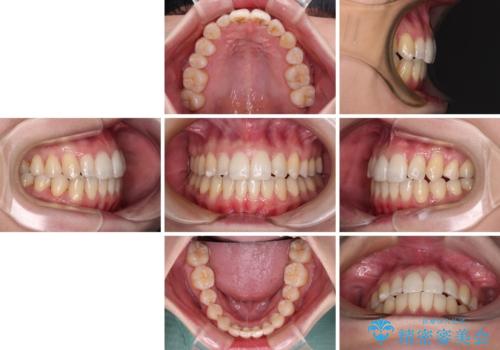

補助装置を併用したインビザラインでの八重歯の抜歯矯正

- 八重歯と奥歯の咬み合わせを気にして来院された患者様です。

インビザラインによる矯正治療を希望されたため、八重歯改善のための抜歯矯正部分は補助装置を併用し、その後はインビザラインにて行うこととしました。

下顎の右側変位が顕著であったため、ワイヤー矯正の方が咬み合わせは改善しやすいのですが、ある程度は時間がかかっても良いとのことであったので、インビザラインにて矯正治療を行うこととしました。

骨格的に下顎が右側に変位していたため、上下正中を合わせることは困難であることは分かっていました。それでも、なるべく合わせるようにとしたため、治療期間は長期間となりました。

長期間とはなりましたが、咬み合わせが改善され、患者様には大変満足していただきました。